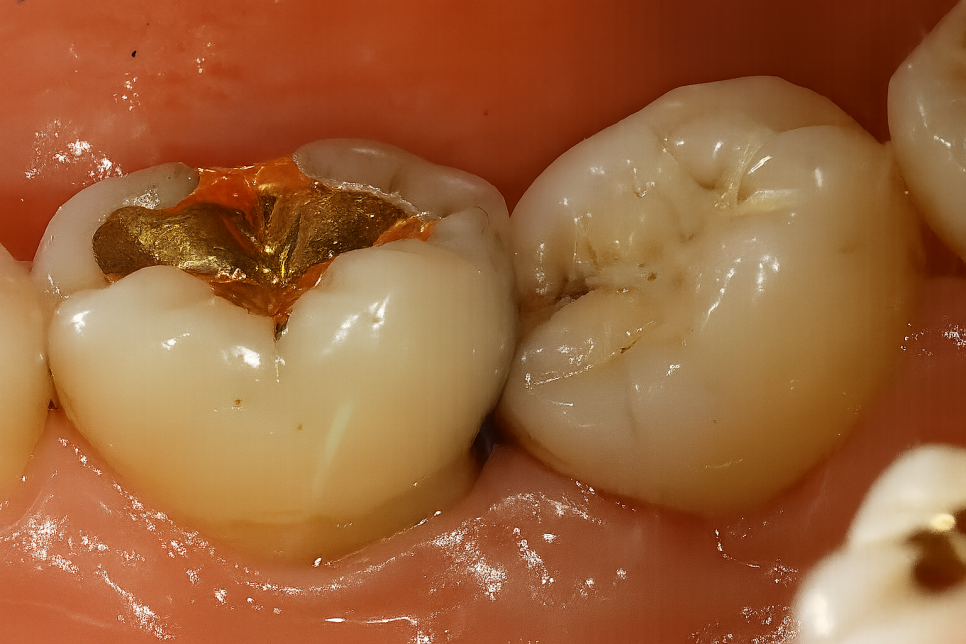

혹시 레진, 인레이, 크라운을 씌운 경험 있으신가요?

아마 대부분 재료나 보철을 수복하신 적 있으실 겁니다.

대부분 치료를 받았으니, 평생 괜찮겠지 생각하시는데

보철에도 수명이 있습니다.

자동차 엔진이나 핸드폰도 일정 기간 사용하면

고장 나서 교체를 해야 되듯이

인레이나 크라운도 정기적으로 확인해 주고

문제가 있다면 교체를 해야 된답니다.

제가 준비한 자료를 보면서 자세히 설명해 드리겠습니다.

우장산역 치과 구강 정보

보철 하방 이차우식

사진을 보시면 기존에 수복한 인레이 주변으로

검게 충치를 확인해 볼 수 있습니다.